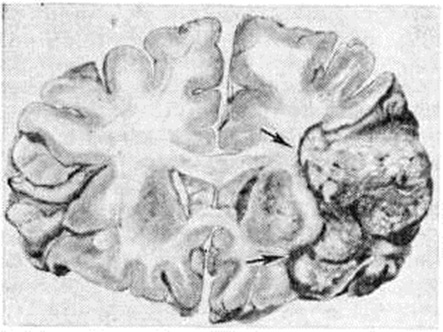

Рис. 5.

Фронтальный срез головного мозга на уровне зрительных бугров с обширным «смешанным» кровоизлиянием (гематома указана стрелками) в левом полушарии мозга с прорывом крови в желудочки.